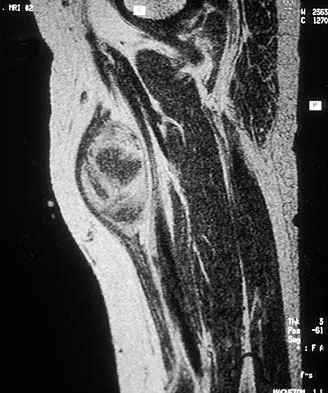

A 10-year-boy has had thigh pain for the past several months. He denies any history of trauma. Examination reveals no soft-tissue mass, and mild tenderness. Figures 33a and 33b show the plain radiograph and MRI scan, and the biopsy specimens are shown in Figures 33c and 33d. What is the most likely diagnosis?